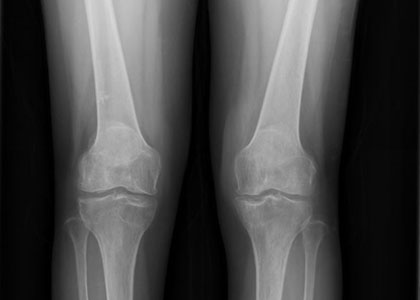

(图:蒲女士入院后CT检查)

患者C-反应蛋白20.15mg/L,血沉55mm/L,血小板531*10∧9/L。而且膝关节肿胀明显,不能伸直,活动受限,关节遭受到严重的破坏,关节面边缘模糊不清,甚至病菌开始向身体其他关节侵犯,软骨下骨开始破坏,关节间隙明显狭窄。